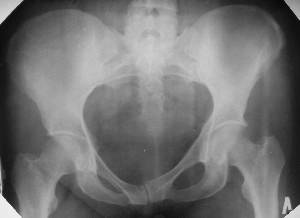

Уважаемые коллеги! Хотел-бы обсудить интерессный, на мой взгляд, случай.На консультацию пришла женщина 45 лет с отводящей контрактурой правого бедра.

Из анамнеза: в ноябре 2002г. оступилась,упалана трап самолета (на верхней площадке, сразу при выходе из салона) на правый тазобедренный сустав, а затем - вниз на землю на ноги и ягодицы. Потеряла сознание от боли. Доставлена в больницу по месту жительства, лечилась консервативно с диагнозом кокцигодиния.На рентгенограмме от 27.11.02г. вывиха копчика не определяется (снимок идентичен представленной R-грамме от28.11.03г., кроме этого есть нормальная R-грамма копчика в боковой проекции).Через три недели стала ходить, но привести правую ногу в тазобедренном суставе не могла. Сейчас ходит отведя кнаружи правое бедро и голень, как ножку циркуля (фото 1). Неврологических нарушений нет. По просьбе врачаможет на 30-40 секунд поставить ноги вместе (фото 2). При этом испытывает сильную тянущую боль и ощущение "вывернутости" в правом тазобедренном суставе. Эти ощущения заставляют вновь отвести бедро. В положении лежа разогнуть бедро полностью не может из-за болей в ягодичной мышце (фото 3). Сгибание также ограничено из-за болей (фото 4). Отведение в положении лежа возможно в том же объеме, что и стоя (фото 5). Заподозрен старый разрыв правого крестцово-подвздошного сочленения.Выполнено R-исследование и КТ(в приложении). По-поводу деформации лонного сочленения выяснен гинекологический анамнез. Роды одни, нормальные в 22 года. Из роддома выписана на 8 сутки, нарушения походки не было, R-графия таза не проводилась. Вопросы на обсуждение: 1. Диагноз либо алгоритм дальнейшего обследования. 2. Лечебная тактика (в первую очередь возможность и целесообразность оперативного лечения).

Отсутствие изменений сустава на КТ и обычных рентгенограммах, стойкие боли и ограничение подвижности в суставе - симптомы, характерные для повреждения ацетабулярной губы. ЯМР с контрастом или без должны прояснить картину.